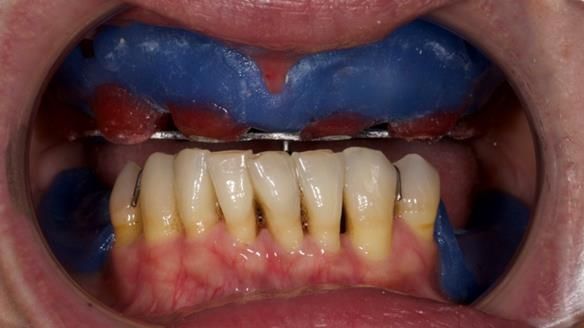

She had previously suffered from generalised periodontitis – stage IV, grade C, currently stable, with reduced attachment across the upper arch.

By the time she came to me, her periodontal condition was stable — but the aesthetics in the upper jaw were very poor.

Dr Syed Abad — my colleague and a Specialist in Periodontics — had successfully stabilised her gum health.

We provided her with an immediate upper denture (Mk 1), followed by a definitive metal-based upper denture (Mk 2). A lower removable partial denture was discussed, to be made only if needed once the upper treatment was complete. However, at review, this wasn’t necessary — Adnana had excellent neuromuscular control and function, even with a shortened dental arch (SDA).